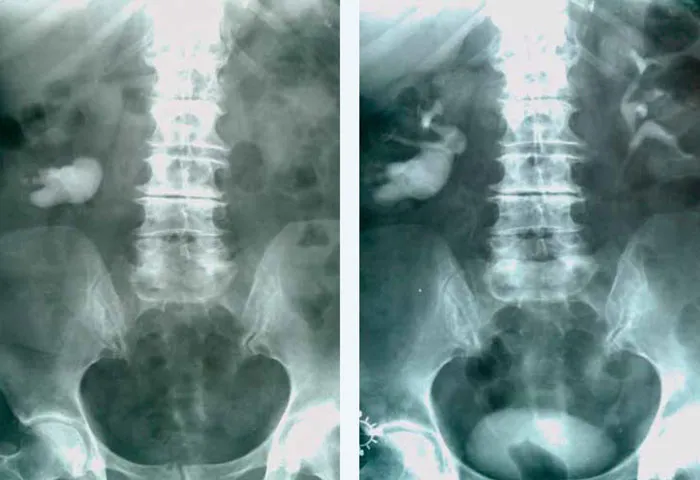

- Badania obrazowe: Najczęściej wykonuje się ultrasonografię (USG) nerek i dróg moczowych, aby ocenić ich budowę, wykryć ewentualne kamienie, torbiele, zwężenia czy zmiany zapalne.